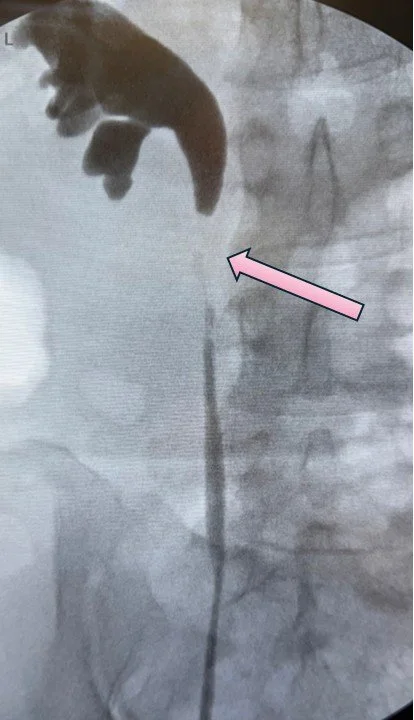

The image below is an x-ray of a patient referred to me with obstruction of the ureter which was caused by radiation therapy for cancer. The very last section of the ureter, just before it connects to the bladder, is very tight. It is another example of a distal ureteral stricture. In this case, the ureter could be directly reimplanted into the bladder without the use of a Boari flap (see case above)